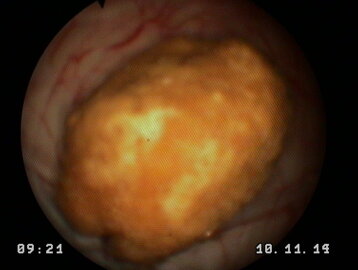

una carrellata di immagini per dare l'idea di cosa è possibile vedere con questo esame

può provocare ematuria e diventare molto pericoloso